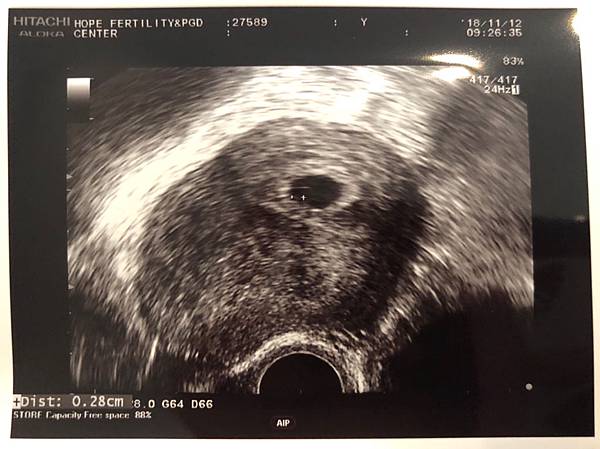

——— 11/12 5W6D ———

今天回診照胚胎和心跳,跟上一次一樣順利的照到,但是寶寶好小好小,小到超音波師在找胚胎的時候自己都說這真的要眼力很好才看的到。今天的胚胎大小大約為0.28cm,沒有特別告知尺寸是否正常,只有說有心跳都是好的。抱著愉悅的心離開,真的希望這一次能一直順利。🙏🏽